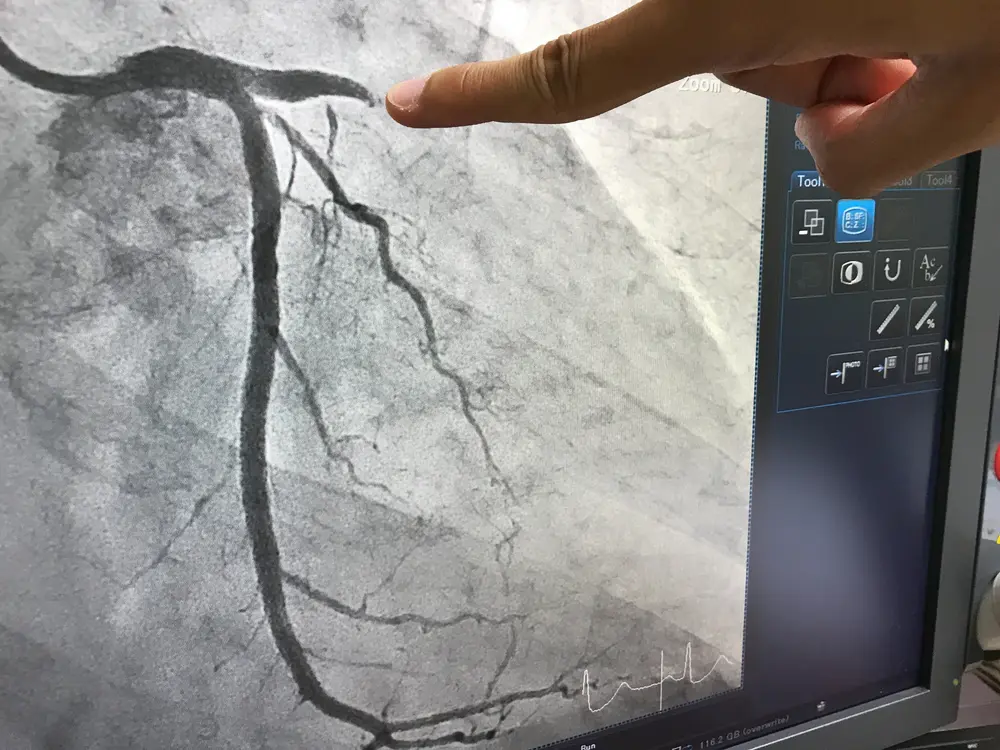

La coronarographie

C'est l’examen qui consiste à faire une radiographie filmée de vos artères coronaires. Cet examen comprend également une séquence évaluant le fonctionnement du ventricule gauche. La coronarographie permet de déceler un ou plusieurs rétrécissements à l’origine des douleurs ou d’un infarctus. Elle rend possible une meilleure adaptation du traitement.

Cet examen utilise les rayons X et un produit de contraste à base d’iode. Son principe consiste à rendre visibles les artères coronaires qui irriguent le cœur. Un cathéter est introduit dans le vaisseau pour injecter le produit de contraste qui se mélange au sang : le système vasculaire devient visible sur les clichés radiologiques grâce aux propriétés radio-opaques de l’iode.